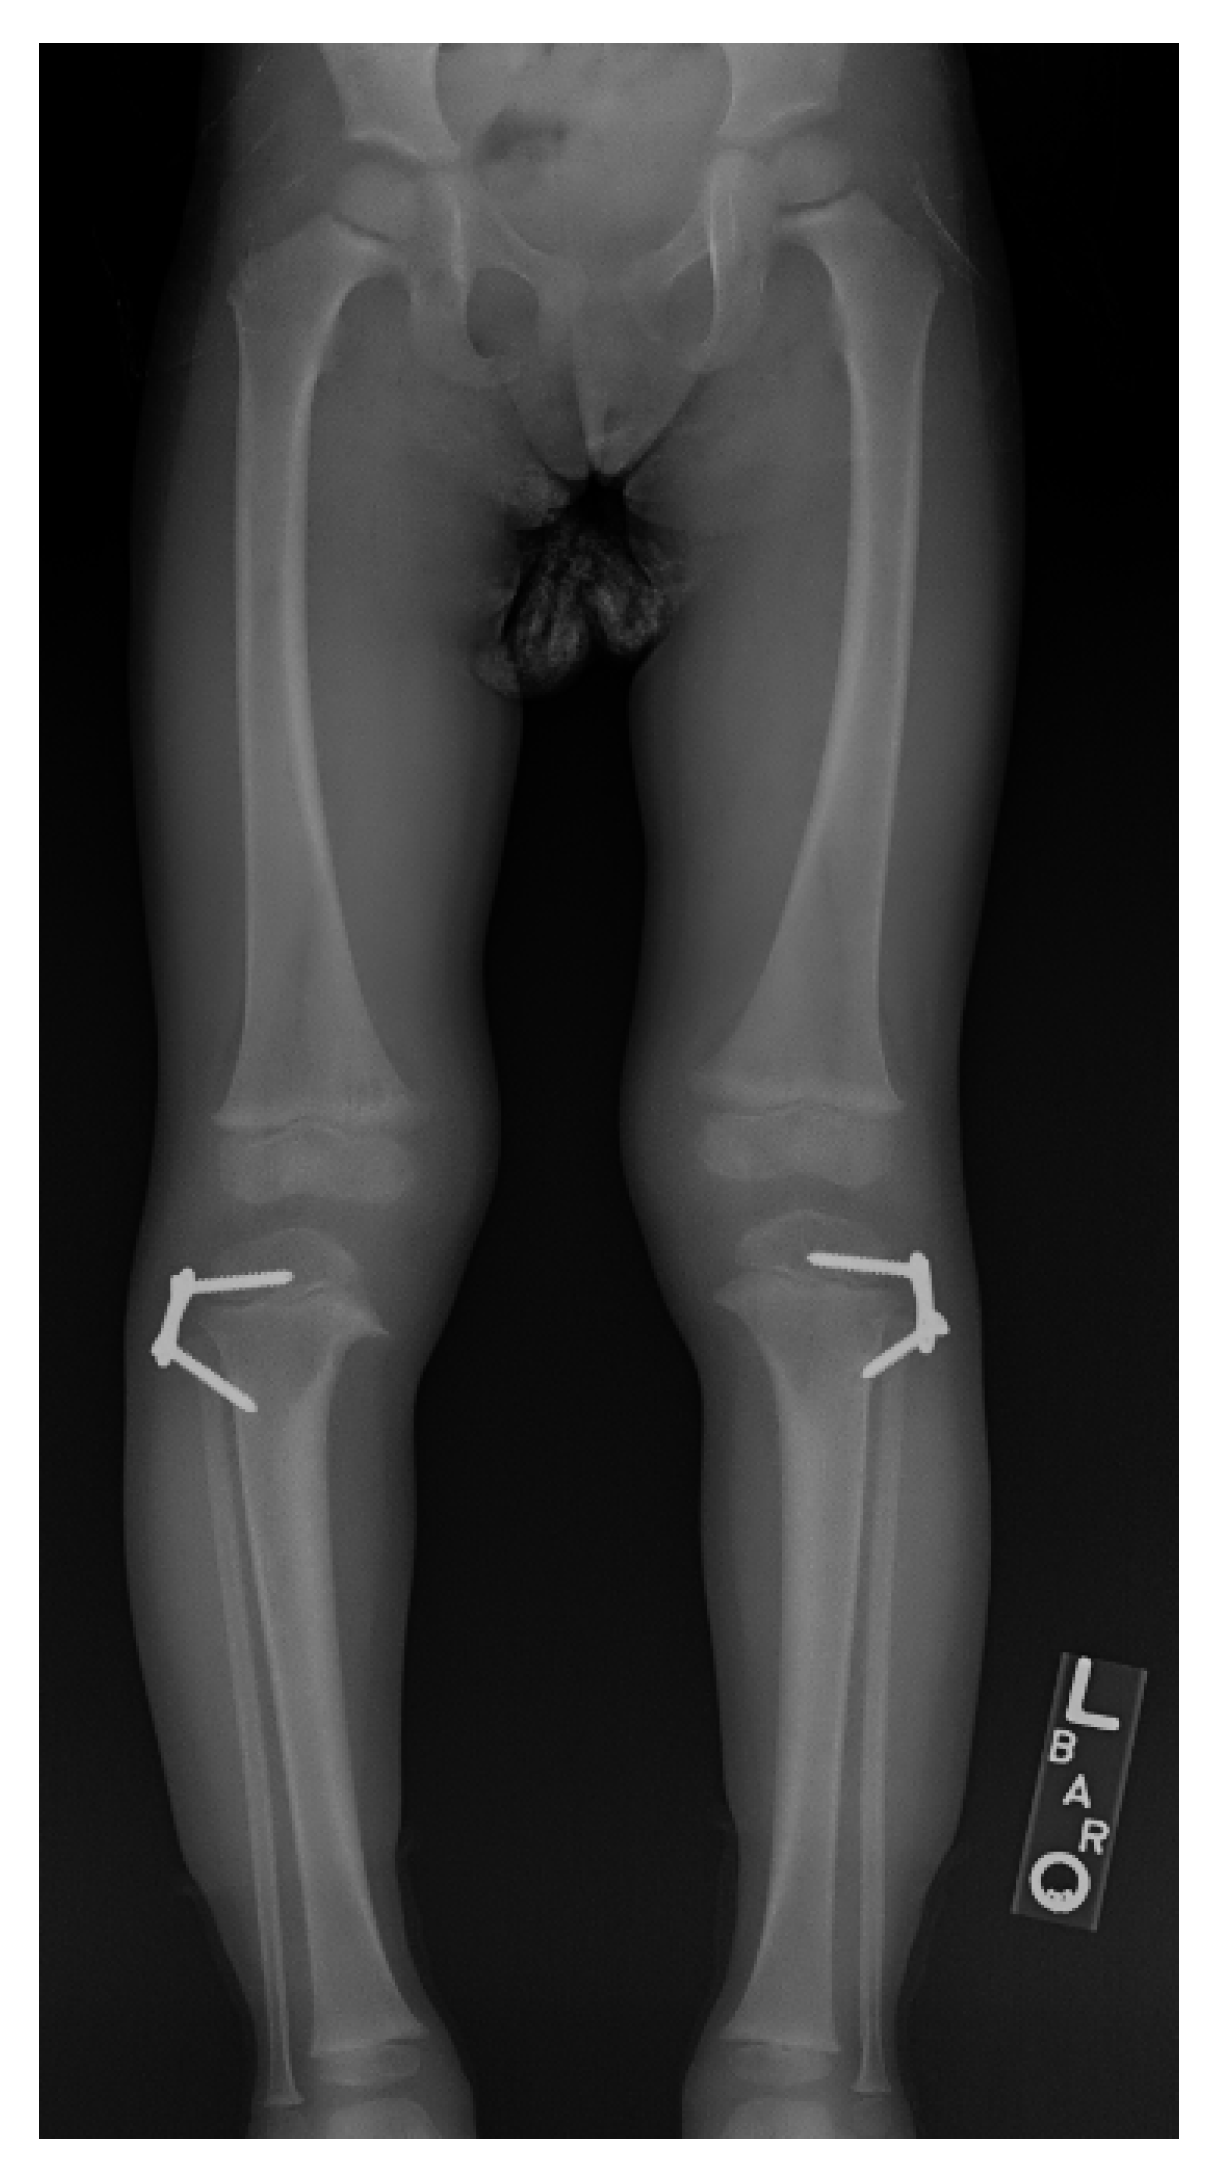

11. Hemi-Epiphysiodesis

17. Gradual Correction with External Fixation

18. Late-Onset Tibia Vara (LOTV)